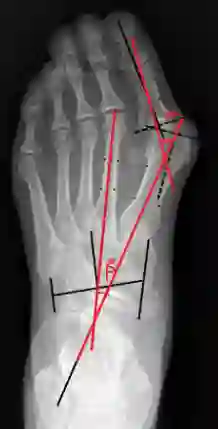

Angular measurements is essential to make a resonable treatment for Hallux valgus (HV), a common forefoot deformity. However, it still depends on manual labeling and measurement, which is time-consuming and sometimes unreliable. Automating this process is a thing of concern. However, it lack of dataset and the keypoints based method which made a great success in pose estimation is not suitable for this field.To solve the problems, we made a dataset and developed an algorithm based on deep learning and linear regression. It shows great fitting ability to the ground truth.